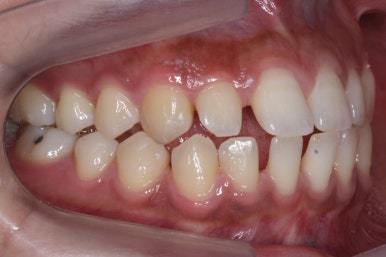

전반적으로 흩어져 있던 틈새를 특정 위치로 모으기 시작합니다.

앞니 사이의 틈을 제일 보기 싫어하실 것 같으므로 앞니 부터 빠르게 틈을 보아줍니다. 대신 작은 어금니 부위로 틈을 모으는 작업을 하게 됩니다.

점점 앞니 사이의 틈이 없어지는 것을 볼 수 있습니다.

앞니 사이의 없어진 틈은 대신 작은 억므니 부위로 모여져 갑니다.

앞니 사이의 틈이 이제 다 모아졌습니다.